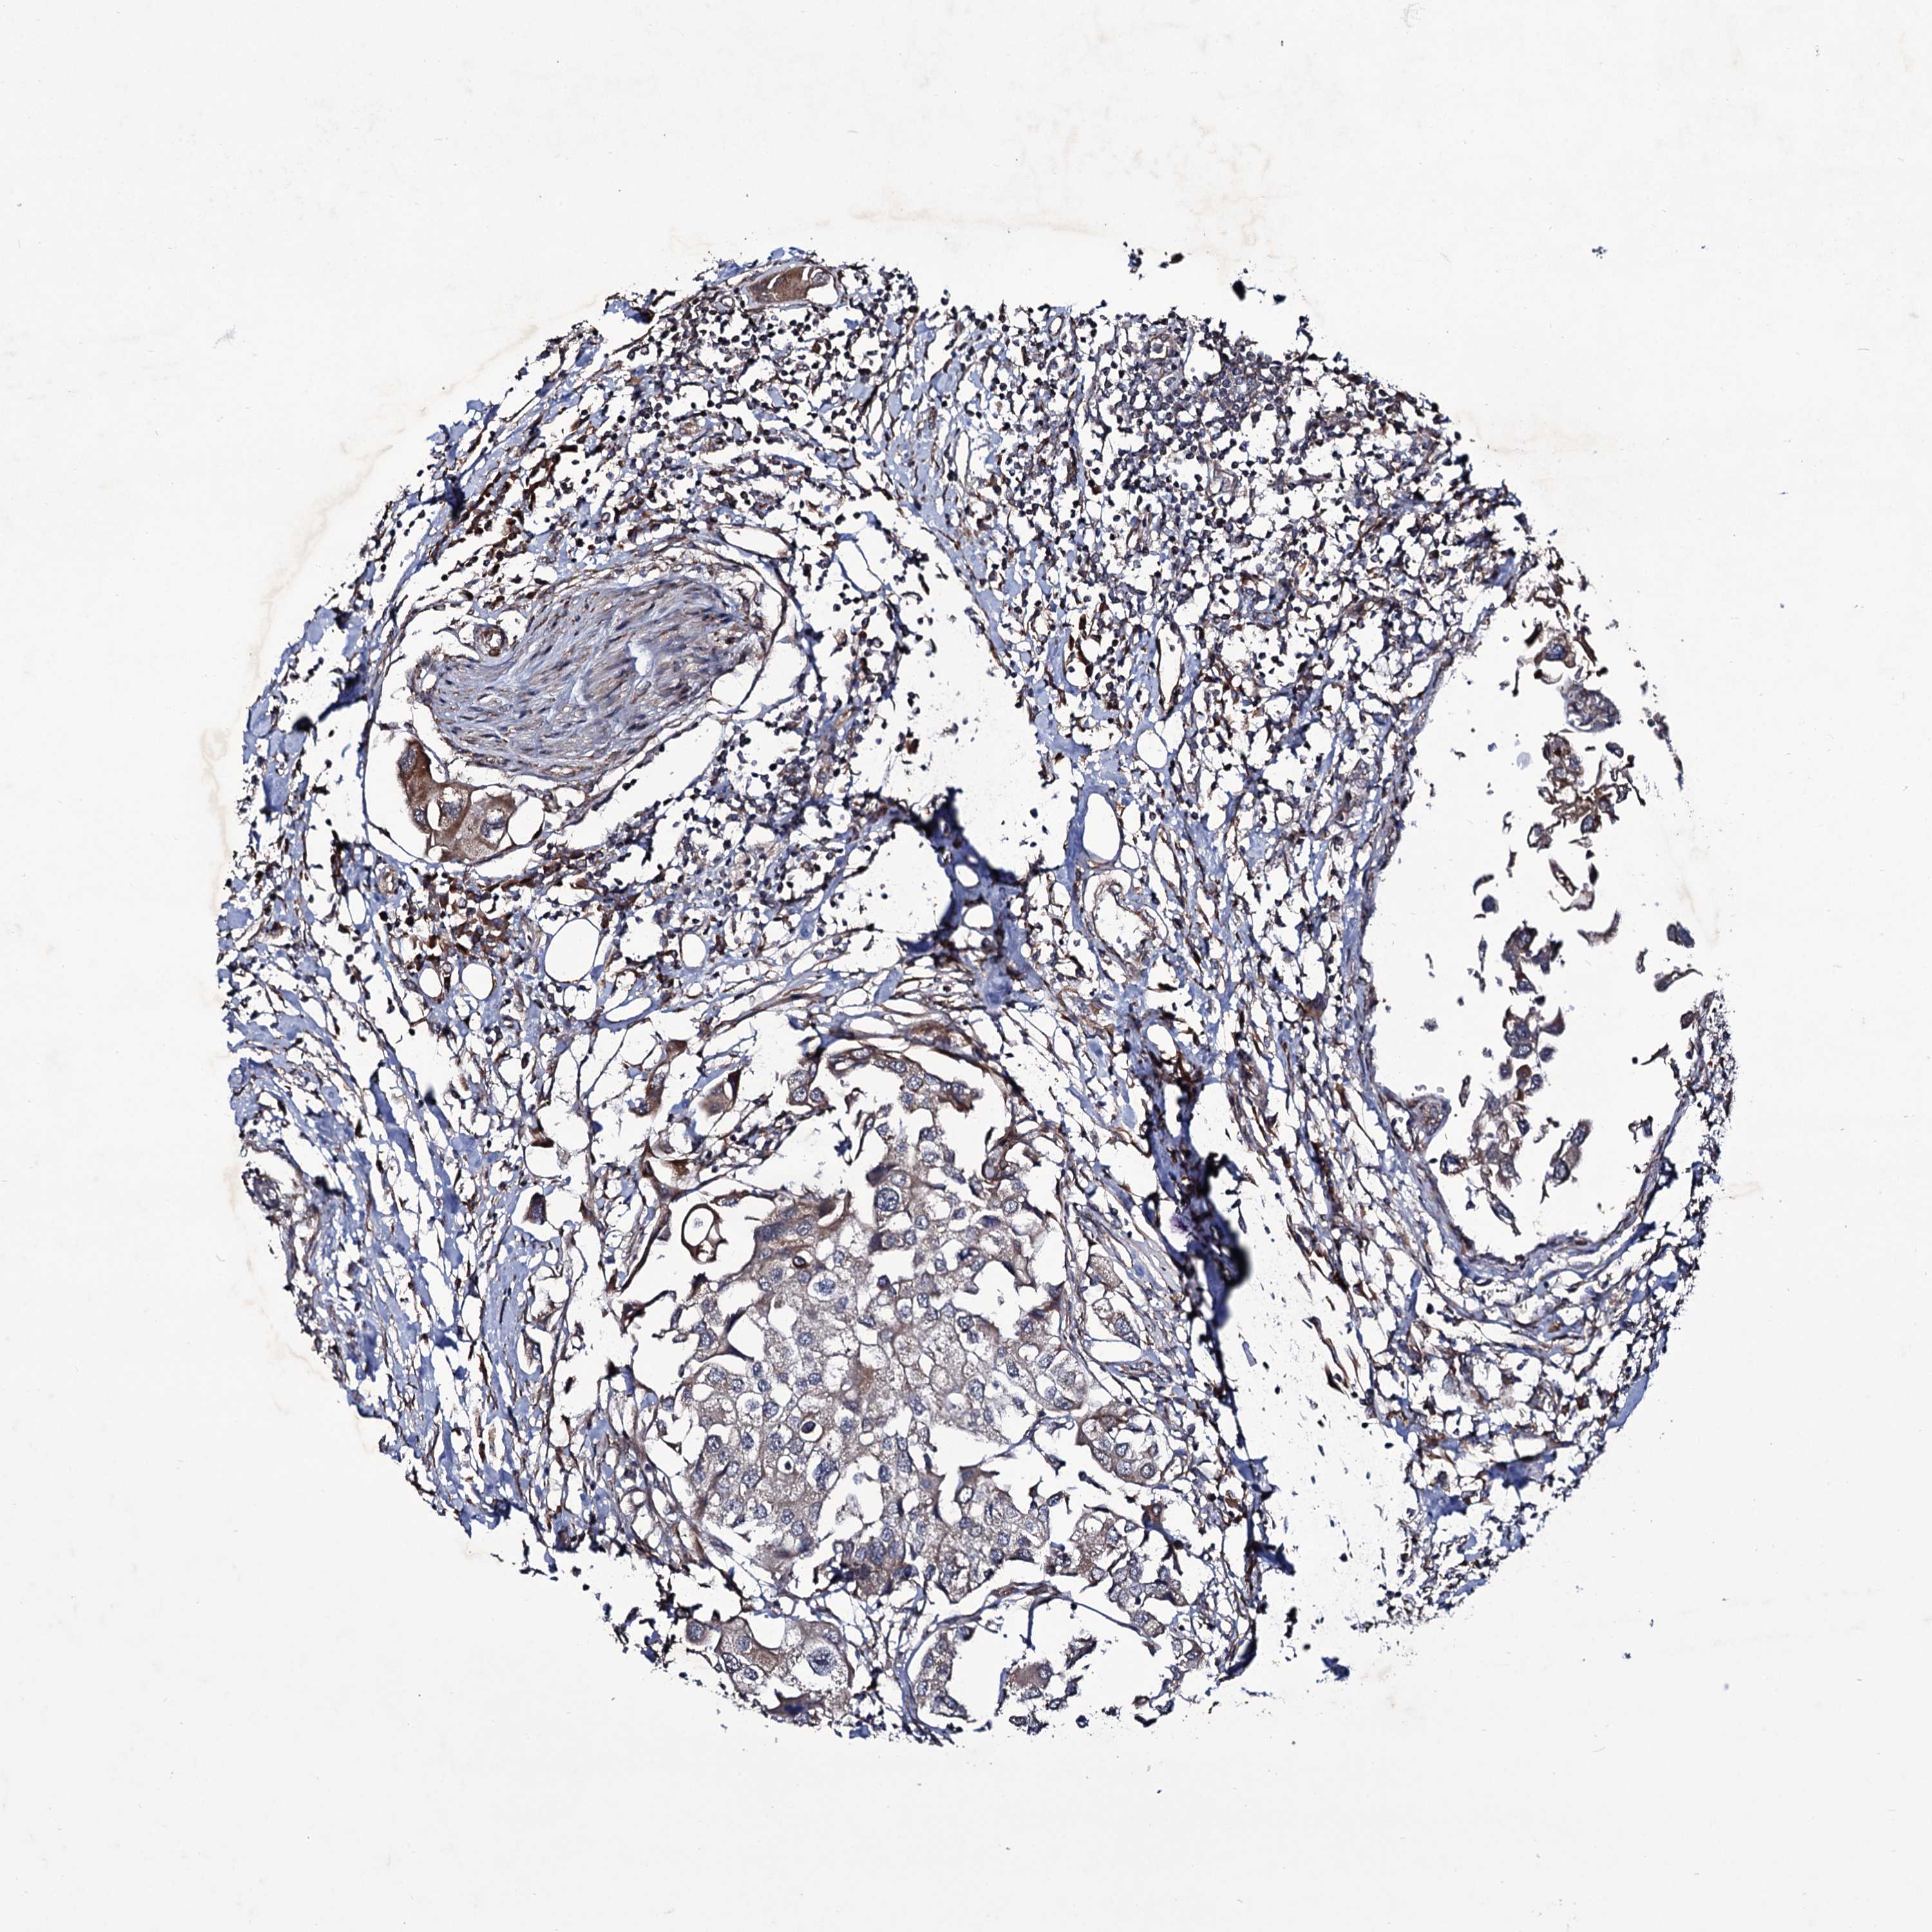

UROTHELIAL CANCER - Protein expressioni

A mouse-over function shows sample information and annotation data. Click on an image to view it in a full screen mode. Samples can be filtered based on level of antibody staining by selecting one or several of the following categories: high, medium, low and not detected. The assay and annotation is described here.

Note that samples used for immunohistochemistry by the Human Protein Atlas do not correspond to samples in the TCGA dataset.

Antibody stainingi

Antibody staining in the annotated cell types in the current human tissue is reported as not detected, low, medium, or high, based on conventional immunohistochemistry profiling in selected tissues. This score is based on the combination of the staining intensity and fraction of stained cells.

Each image is clickable and will lead to virtual microscopy that enables deeper exploration of all samples and also displays staining intensity scores, fraction scores and subcellular localization as well as patient and tissue information for each sample.

Antibody HPA039366

Staining

High

Medium

Low

Not detected

Intensity

Strong

Moderate

Weak

Negative

Quantity

>75%

75%-25%

<25%

None

Location

Urothelial carcinoma, High grade

Urothelial carcinoma, Low grade

Urothelial carcinoma, NOS